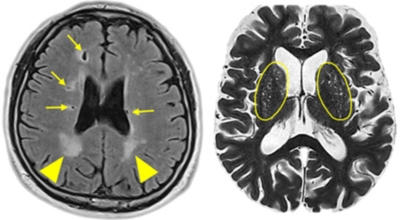

뇌 속에 혈액을 제공하는 혈관이 있는데, 이 혈관이 막히면 정상적으로 지급되어야 할 만큼의 혈액이 뇌까지 도달하지 못하여 뇌조직이 제 역할을 수행하지 못하는 것을 말해요. 이 시간이 지속될 경우 몸의 여러 곳에 지장이 생기며 이것을 뇌경색이라고 해요.

뇌경색의 주된 원인은 혈전입니다. 혈전이란 혈관 속에 피가 굳어진 덩어리를 얘기하는데 이것이 혈관을 막는 것이 뇌경색에 큰 영향을 준다고 해요. 평균적으로 많이 나타나는 연령대는 5~60대입니다. 뇌경색은 양쪽 뇌에 모두 생기는 것이 아니라 주로 한쪽 뇌에만 발생하지만, 주로 한쪽 팔다리가 마비되거나 얼굴 근육이 굳어버리기도 해요.

뇌경색이 생기는 원인은 아주 다양해요. 뇌경색은 뇌의 혈관이 막혀 뇌의 일부가 죽는 질병을 말하는데 주로 뇌경색의 원인은 혈전이며, 혈전으로 인해 뇌혈관이 막히는 위험 인자는 혈전을 발생하게 해요. 또한 동맥경화나 심장병, 혈관박리, 뇌혈관 기형 등으로 말미암아 생기게 될 수 있다고 하며 대부분이 60세 이상의 고령층에서 빈번히 나타나는 질환으로 알려져 있답니다.